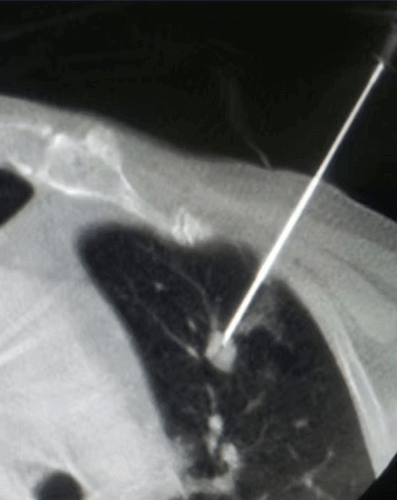

In the same patient, 2 metastases that grew after 2 years were cryoablated using 2 needles. Three months later, the control CT shows that both masses have shrunk and become a residue.